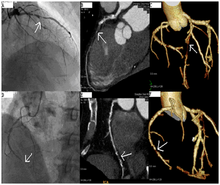

CT angiography can act as a less invasive alternative to Catheter angiography. Instead of a catheter being inserted into a vein or artery, CT angiography involves only the injection of a CT-visible dye into the arm or hand via an IV line. CT angiography lowers the risk of arterial perforation and catheter site infection. It provides 3D images that can be studied on computer, and also allows measurement of heart ventricle size. Infarct area and arterial calcium can also be observed (however those require a somewhat higher radiation exposure). That said, one advantage retained by Catheter angiography is the ability of the physician to perform procedure such as balloon angioplasty or insertion of a stent to improve blood flow to the artery.[3]